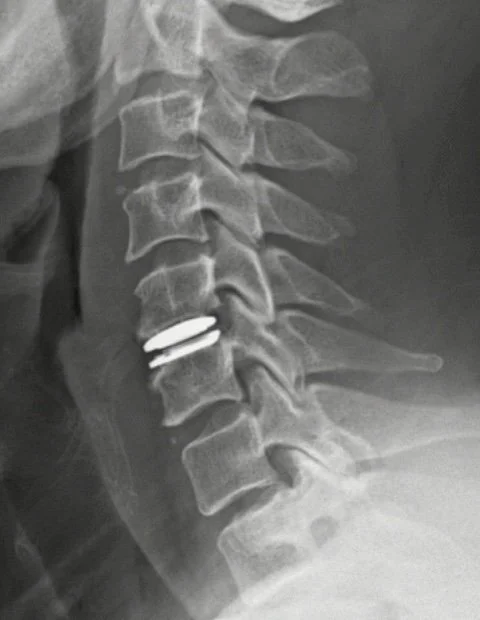

Procedimiento quirúrgico en el cual se realiza la extracción del disco intervertebral herniado o dañado y se sustituye por una prótesis artificial del disco para preservar la movilidad en ese nivel vertebral.

Procedimiento quirúrgico en el cuál se realiza la extracción del disco intervertebral herniado y en su lugar se coloca una prótesis artificial de disco intervertebral.